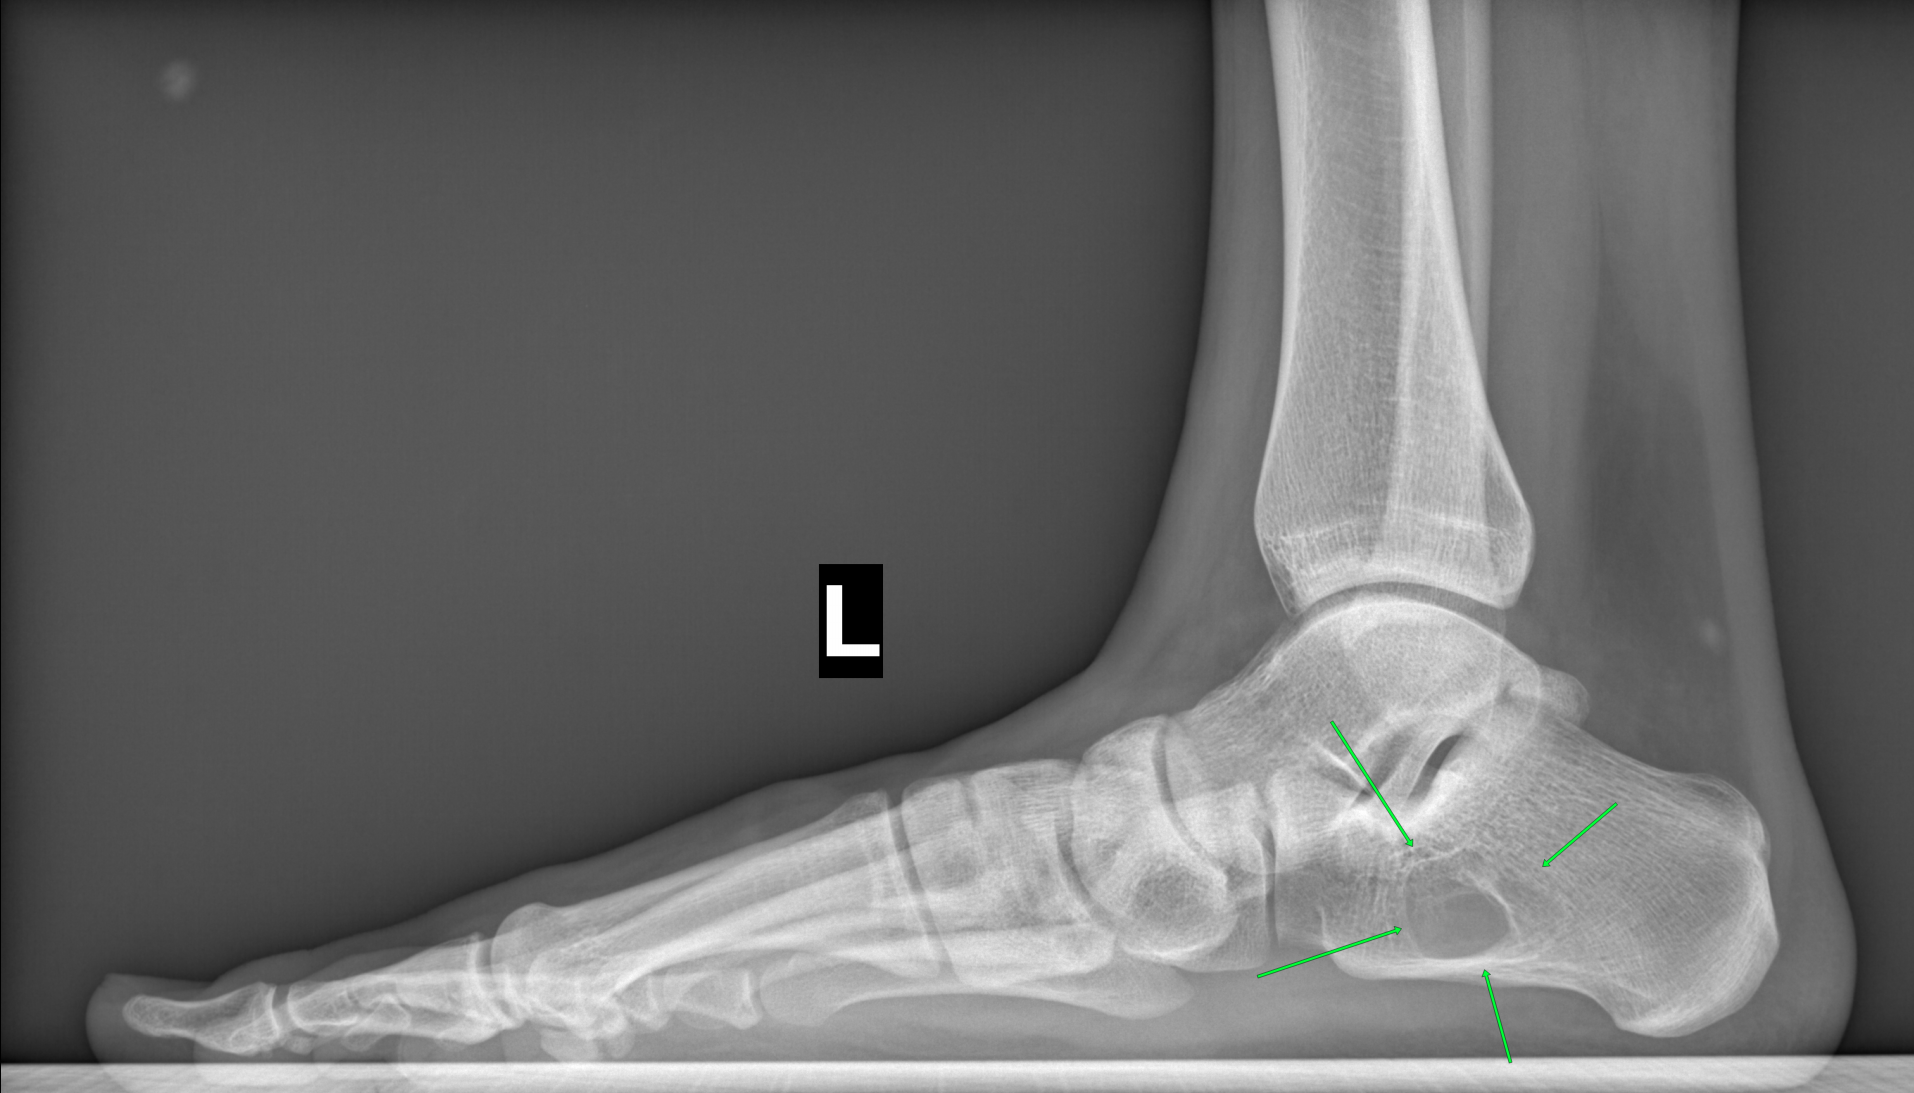

На Р-грамме левой стопы с нагрузкой: в структуре пяточной кости отмечается зона просветления костной ткани размером 29х27х17мм (точные размеры по данным КТ, которая была пройдена призывником),неправильной овоидной формы, с склеротическим контуром, соответствует кисте левой пяточной кости.

3)Киста левой пяточной кости: с учетом ее крупного размера, имеется риск возникновения патологического перелома пяточной кости, риск патологического перелома возникает когда размер кисты составляет примерно 50% или более диаметра кости, как в данном случае. Категория годности по ст.10а-Д(не годен к военной службе),однако зачастую при данном диагнозе ставится ст.10б-В(ограниченно годен к в/сл),это делается для того чтобы не "портить" военный билет категорией Д.